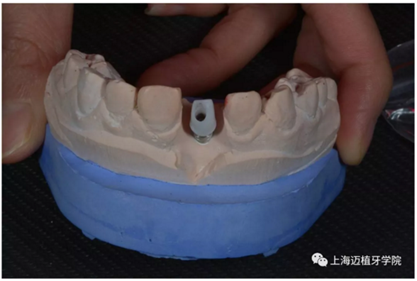

轉(zhuǎn)移模型

取工作模型

氧化鋯個(gè)性基臺(tái)